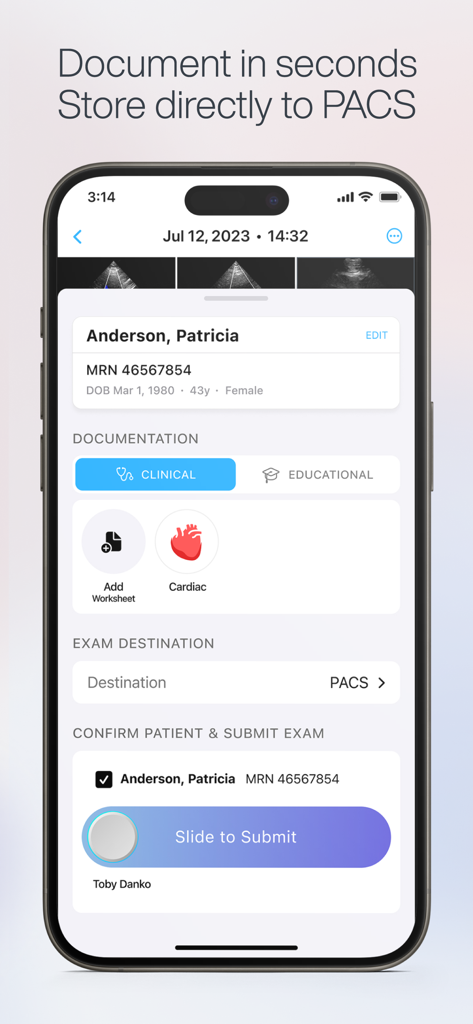

Exo Iris™ redefines the medical imaging ecosystem, blending high-performance proprietary silicon technology with real-time AI to deliver clinical answers when seconds count.